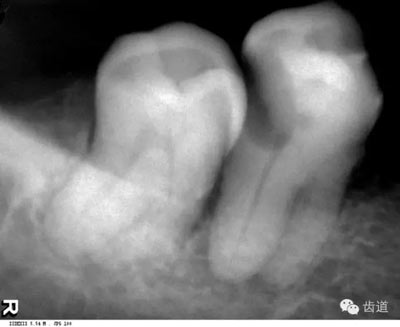

是上下頜骨包圍牙根的突起部分,又稱牙槽突或牙槽嵴。X線片上牙槽骨所顯示的密度較牙低。上牙槽骨的密質(zhì)骨薄,松質(zhì)骨多,即骨小梁數(shù)目多,相交處呈密度高的點狀影像,骨髓腔則呈點狀密度低的影像,固上牙牙槽骨的骨小梁結(jié)構(gòu)X線片上呈顆粒狀影像;

牙槽骨:下牙槽骨密質(zhì)骨厚而松質(zhì)骨少,骨小梁多呈水平方向排列,骨髓腔呈三角形和大小不等的圓形密度低的影像,所以下牙槽骨的骨小梁結(jié)構(gòu)呈網(wǎng)狀結(jié)構(gòu)

即固有牙槽骨,是牙槽骨的內(nèi)壁,圍繞牙根,骨質(zhì)致密而薄,X線片上顯示為包繞牙根的連續(xù)不斷的密度高的線條狀影像。

是介于牙槽窩和牙骨質(zhì)之間的結(jié)締組織。牙周膜的厚度一般在0.15~0.38mm之間。X線上顯示為包繞牙根連續(xù)不斷的密度低的線條狀影像,其寬度均勻一致